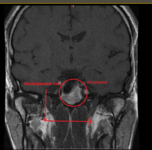

Weil ich Angst habe das mein Hirn von Schwermetalle geschädigt ist, und die Radiologie es nicht sieht ( weil die Microweiße Punkte im Hirn keiner Bedeutung zuweisen, diese sich aber über kurz oder Lang vergrößern können) habe ich die CD's der beiden MRT's aus den letzten beiden Jahren angefordert und möchte mittels Daunderers Bildmaterial mein Hirn mal vergleichen. Vielleicht erkenne ich ja Auffälligkeiten.

Um ein Microadenom auszuschließen erfolgt MRT 3 in den nächsten 4-8 Wochen. Dabei begleitet mich ein Neurologe der mir dann hoffentlich auch mal Diazepam verschreibt. Ich möchte das Zeug unbedingt testen und in wirklich schwierigen Zeiten so wie gestern und heute einfach mal 2 Tage nehmen um ne Pause von meinen Rückenproblemen zu haben. Plan sind 2-4 Einnahmezyklen pro Monat jeweils über 2 Tage um keine Abhängigkeit zu riskieren. Die Nebenwirkungen sind deutlich milder als bei Ortoton.